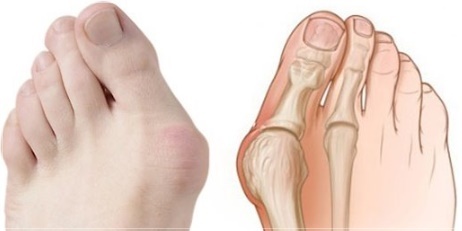

무지외반증은 엄지발가락이 둘째발가락 쪽으로 심하게 휘어져 엄지발가락 관절이 안쪽으로 돌출된 상태를 말하며, 심한 경우에는 엄지발가락이 둘째발가락과 엇갈리는 정도까지 돌아가기도 합니다. 특히 앞이 좁고 굽이 높은 신발을 자주 신는 여성에 흔한 대표적인 족부 질환입니다.

엄지 발가락의 튀어나온 관절부분(건막류)이 신발에 눌려 통증을 호소하는 것이 주 증상이나 엄지발가락이 둘째발가락 쪽으로 휘어져 있고, 관절이 안쪽으로 돌출되어 있습니다. 돌출된 관절은 서 있거나 걸을 때 자극을 받아 빨갛게 변하고 굳은살이 잡히며 염증과 통증이 발생합니다. 엄지발가락이 제 역할을 하지 못하니 발의 다른 부위에도 통증이 생기고 심해지면 발 모양의 변형, 허리의 통증 등이 발생합니다.